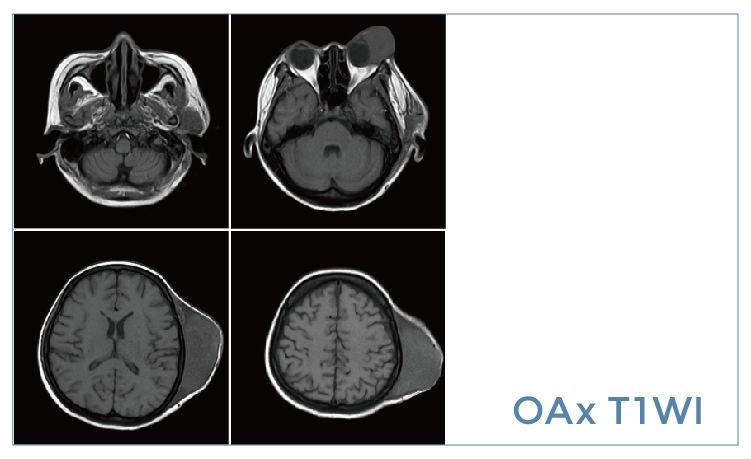

【朗润影像档案】20191115磁共振影像病例结果讨论

【朗润影像档案】磁共振影像病例分享(编号20191115)

【朗润影像档案】20191108磁共振影像病例结果讨论

【朗润影像档案】磁共振影像病例分享(编号20191108)

【朗润影像档案】20191101磁共振影像病例结果讨论

【朗润影像档案】磁共振影像病例分享(编号20191101)

【朗润影像档案】20191018磁共振影像病例结果讨论

【朗润影像档案】磁共振影像病例分享(编号20191018)

【朗润影像档案】20190927磁共振影像病例结果讨论

【朗润影像档案】磁共振影像病例分享(编号20190927)

【朗润影像档案】20190920磁共振影像病例结果讨论

【朗润影像档案】磁共振影像病例分享(编号20190920)